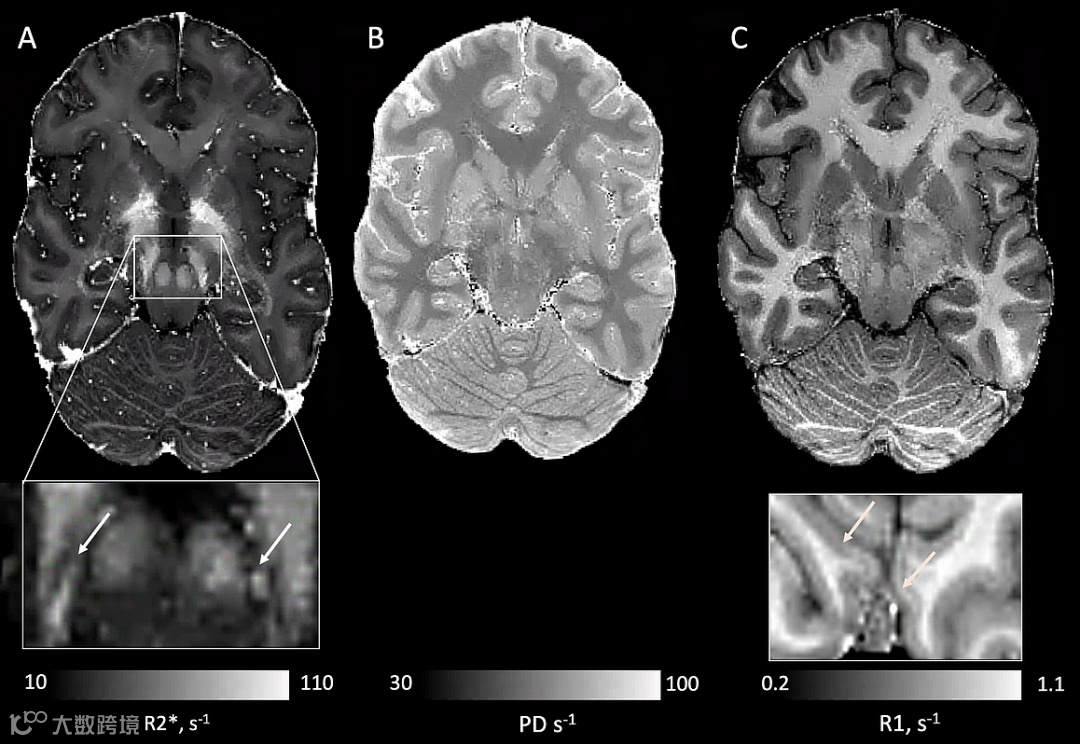

Ultra-high-resolution (0.65 mm) quantitative multi-parameter maps (MPM) acquired with maximum acceleration (CS factor 10), resulting in a total acquisition time of 8 minutes using a 64-channel coil.

High-quality qMRI data were obtained within a clinically feasible time frame, allowing for the quantification of submillimeter structures across neocortex, subcortex, and brainstem.

Subnuclei within SN are visible on quantitative R2* maps (arrowed).

Fine details of cortical myeloarchitecture are also visible (e.g. Stria of Gennari in primary visual cortex, arrowed).